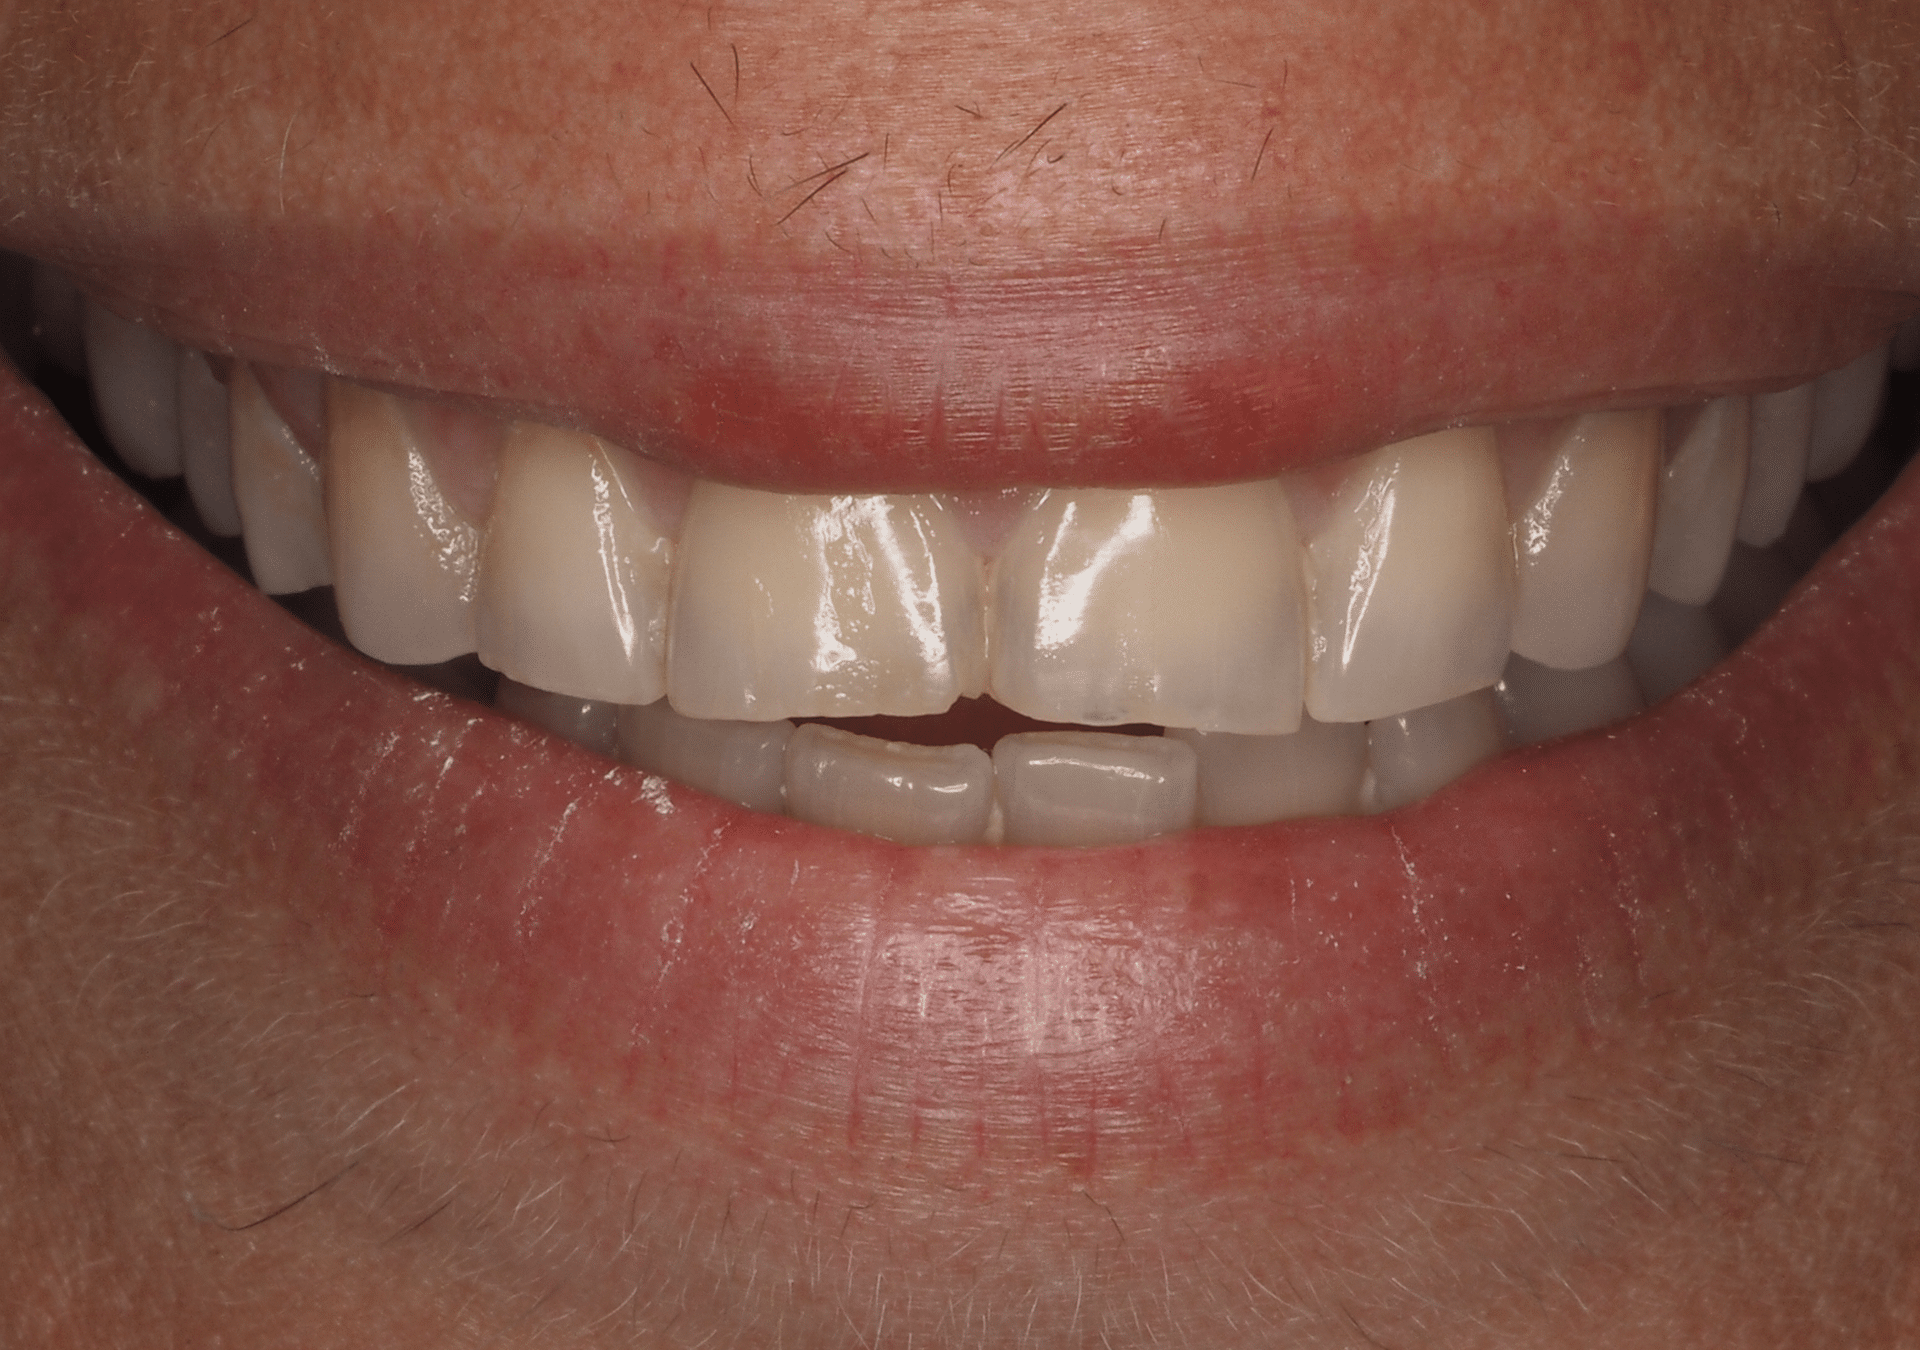

Caso 1

Blanqueamiento con técnica mixta domicilio/clínica para tratar paciente con tetraciclina severa. Posterior al blanqueamiento, se realiza el cambio de las restauraciones de resina envejecida por carillas de cerámica en los dos centrales superiores.